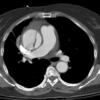

Ao Diss 1b

Date: 01/21/2006

Views: 2999